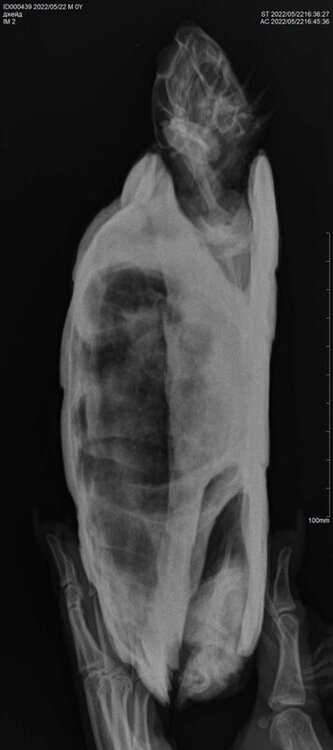

9. Вызов герпетолога на дом 21.04, ввел такие препараты: Тиенам, ронколейкин, гемобаланс, траумель, дюфалайт, катозал внутримышечно в попу, в каком количестве не знаю. Прописал Байтрил 2,5  1-2 капли припаивать 2 раза в день,10-14 дней. Гамавит 2-4 капли припаивать 2 раза в день 14 дней. Выполнил, параллельно через неделю начал закапывать в глаза тобрекс по 1 капле раз в день. Две недели черепаха часто дышит тяжело, с открытым ртом, издавая шипение, появляется какая то слизь. Соплей нет, неактивна, глаза постоянно закрыты, аппетит отсутствует. Находясь в воде выпускает пузыри изо рта. Делал периодически ромашковые ванны по полчаса, температура 28- 29 градусов и параллельно пытался кормить, ела по три четыре кусочка рыбы хек, креветки. 4 дня назад сделан укол Элеовита внутримышечно по калькулятору, два раза сделаны уколы борглюконата кальция подкожно, три раза поставлен зонд и введен Эспумизан по калькулятору. Вчера сделан рентген в двух проекциях. Требуется расшифровка. Улучшения состояния черепахи в течение всего месяца лечения нет, только ухудшение. Еще вспомнил, что перед заболеванием черепахи сломался нагреватель воды, и похоже всю ночь и день черепахи мерзли, температура воды опустилась наверное градусов до 18. Думаю это стало триггером к заболеванию, плюс нездоровое питание и еще не совсем правильное содержание. Записался к Токаревой Марии в Зоостатус на субботу 29. Хотел узнать продолжать ли лечение кальцием и Эспумизаном или ждать до очного осмотра? Спасибо.

@Nadbull к сожалению я снимки читаю плохо. Из того, что я вижу - сильные газы в жкт. Есть она с такими точно не будет.